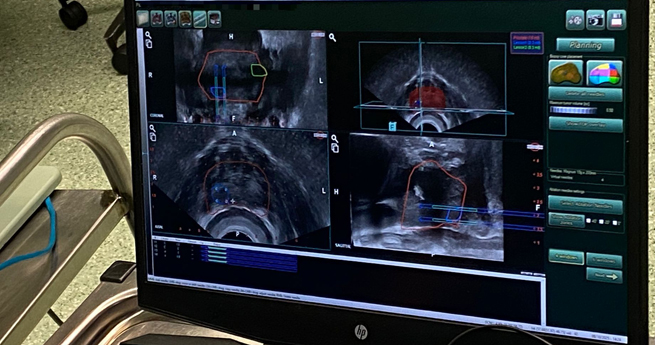

A biópsia de fusão, realizada sob anestesia geral, no bloco operatório, é considerada o “padrão de ouro” no diagnóstico desta doença. A ULS Médio Tejo salienta que, ao contrário da técnica clássica, guiada unicamente por ecografia, "a biópsia de fusão utiliza igualmente as imagens da ressonância magnética multiparamétrica da próstata, que permitem identificar as lesões suspeitas. Estas imagens são sobrepostas com as da ecografia, permitindo biopsar com precisão lesões de 4 a 5 milímetros".